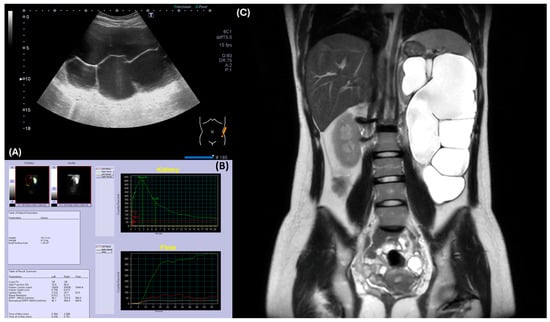

At her first hematology clinic visit at 17 years, 2 months, and 22 days old, she denied headache, dizziness, or fatigue but a flushed face was noted. To rule out oxygen desaturation, we checked her oxygen saturation, which was normal. To determine the etiology of polycythemia, the complete blood count revealed an increased hemoglobin level of 19.9 g/dL with normal leukocyte/differential counts and platelet counts. We also checked the serum EPO level with the IMMULITE® 2000 EPO (Siemens Healthcare, Erlangen, Germany) assay following the instruments to distinguish between primary and secondary erythrocytosis. Briefly, serum was collected in the morning, stored at 2–8 °C, and measured using a chemiluminescent immunometric assay on the IMMULITE 2000 system, which detected EPO levels through a sandwich complex formation and subsequent light emission. The normal to low EPO level (8.5 mIU/mL, normal range: 4.3–29.0 mIU/mL) was identified. Repeated measurement of EPO levels 2 months later confirmed the observation (11.1 mIU/mL). Bone marrow aspiration and biopsy to rule out myeloproliferative neoplasm showed normocellular marrow without evidence of myeloproliferative neoplasm. The bone marrow chromosome analysis was normal. Molecular tests for specific genetic mutations, including JAK2, CALR, BCR/ABL, and MPL were all negative. An abdominal ultrasound, performed due to a palpable abdominal mass, identified her severe left hydronephrosis (Figure 2A).

Figure 2. Radiographic evaluation of the left kidney revealed hydronephrosis and ureteropelvic junction obstruction. (A) Abdominal ultrasound demonstrated severe hydronephrosis in the left kidney. (B) Renal MAG-3 study indicated poor function of the left kidney, precluding assessment of obstruction. (C) MRI confirmed severe left hydronephrosis with a thinned renal cortex, suggesting ureteropelvic junction obstruction.

For her left hydronephrosis, a voiding cystourethrogram was performed to rule out vesicoureteral reflux, and it showed no abnormalities. To check renal function, serum creatinine was 0.6 mg/dL and BUN was 13 mg/dL. However, the renal MAG-3 scan (SignaTM Artist 1.5T, GE healthcare, Chicago, IL, USA) demonstrated markedly impaired left renal function, making it difficult to assess for obstruction (Figure 2B). An abdominal MRI confirmed severe hydronephrosis with a paper-thin left renal cortex, suggesting ureteropelvic junction stenosis as the underlying cause (Figure 2C).